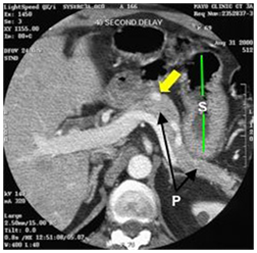

Figure 7a CT scan showing an insulinoma (white dot pointed to by yellow arrow) in the body of the pancreas (P with arrows pointing to the body and tail of the pancreas). The stomach (S with green lines up and down) has air (black) and fluid (darker gray) with it (stomach wall at end of lower green line). 42

Figure 7b CT scan showing insulinoma (white dot pointed to by yellow arrow) in junction of head and uncinate portions of pancreas. Just to the right of the insulinoma is the portal vein (white with "tail"–vein from the spleen joining it) carrying blood from intestine and pancreas to liver. 42